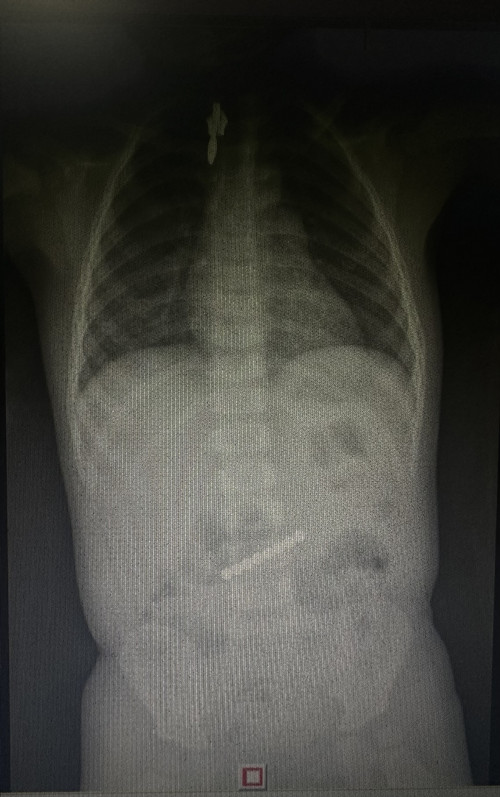

五颜六色的磁力珠对于年龄小的孩子来说有着十足的吸引力,但可能也是致命的威胁。岳阳1岁的萱萱因误食哥哥的磁力珠玩具被父母送来捷克论坛 小儿消化内科求诊,经检查发现其消化道内有8颗磁力珠,这些磁力珠连成一排已达到胃十二指肠,接诊的龙毅副主任医师为萱萱急诊内镜下取出才脱离危险,昨日,萱萱已顺利出院。

龙毅副主任医师介绍,单个磁珠如果到达肠道后一般可自行排出,多个磁珠易相互吸附导致肠道穿孔,腹膜炎和肠缺血、坏死,要紧急取出。他表示,儿童误食异物是儿童意外伤害的主要原因之一,消化道异物发生多见于4岁以下儿童,这个年龄阶段的孩子对什么都很好奇,缺乏安全意识,常常是拿到东西就往嘴里放。儿童消化道异物种类复杂、多样,其中以硬币类异物所占比例最高,其次为电池、各类钉子、磁铁、首饰、果壳、骨碎片,还有塑料棒、笔帽、玻璃珠、毛发等不规则物体,危害较大的三大异物分别为尖锐异物、纽扣电池、磁力珠。儿童消化道异物内镜是首选治疗,异物因大小、形状不同、性质不同,可以造成不同的伤害,如消化道穿孔、出血、化学物质灼伤等危险情况,如果异物进入下消化道以后可以尝试自行排出,如不能排出,必要时要行外科手术取出。